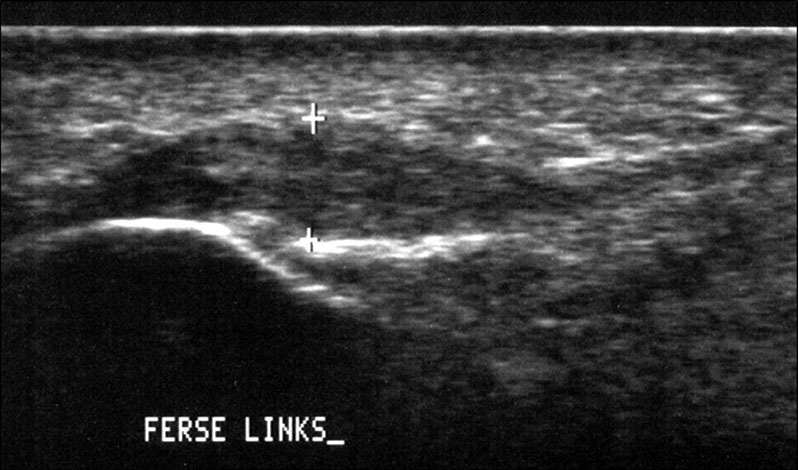

Diagnostik

Die Sonographie zeigt im Falle einer Plantarfasziitis eine Verdickung der Plantarfaszie 24. Sie tritt etwas verzögert nach stattgehabter Überlastung und dem Schmerzbeginn auf und ist in ihrem Ausmaß ein guter Indikator für die Schwere der Erkrankung und die zu erwartende Behandlungsdauer. Die Rückbildung der Verdickung benötigt auch nach erreichter Schmerzfreiheit Wochen bis Monate.

In Abhängigkeit des gesamten klinischen Bildes und der Vorgeschichte kann ein MRT z.B. zum Ausschluss einer Stressfraktur oder Ruptur der Plantarfaszie erforderlich werden. Es hat sich bewährt, in Fällen eines mehrmonatigen Krankheitsverlaufes und sonographisch verdickter Plantarfaszie >8mm (Normwert <4mm) vor Therapiebeginn ein MRT zum Ausschluss von Teilrupturen durchzuführen. Obwohl auch in diesen Fällen eine Stoßwellentherapie erfolgen kann, ist eine derartige Information aus juristischen Gründen von Bedeutung.